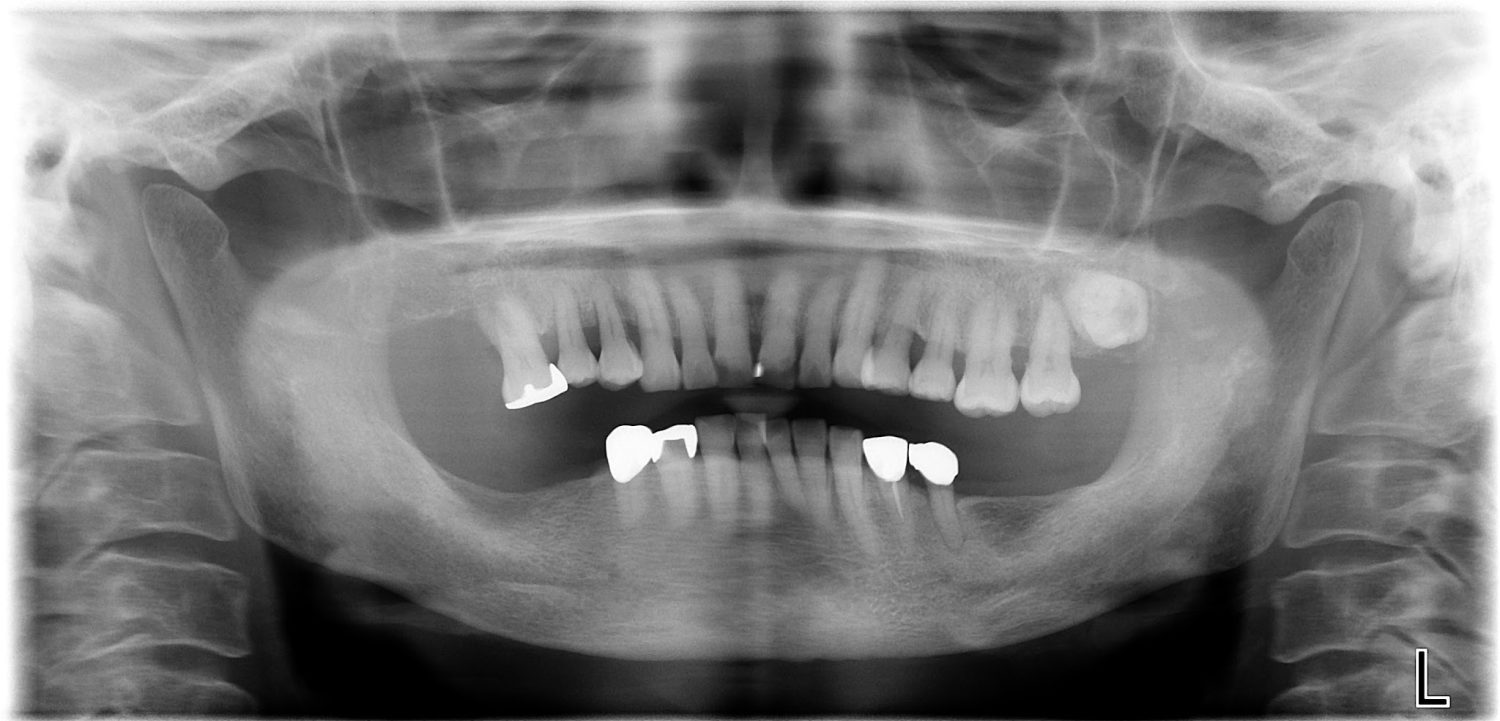

インプラント治療の症例紹介③

Before

After

主訴

むし歯の治療

治療内容

保存不可能な歯の抜歯

下顎にインプラント埋入し咬合再構成

治療費

2,688,400円(税込)

治療期間

14か月

治療回数

21回

想定されたリスク

※上部構造の形態が複雑になるため清掃が難しくなる。インプラント周囲炎の恐れがありました。

多数歯う蝕および多数歯欠損による咬合崩壊、保存不可能な歯の抜歯により上下無歯顎に。下顎に6本インプラント埋入する事で咬合再構成を行った。